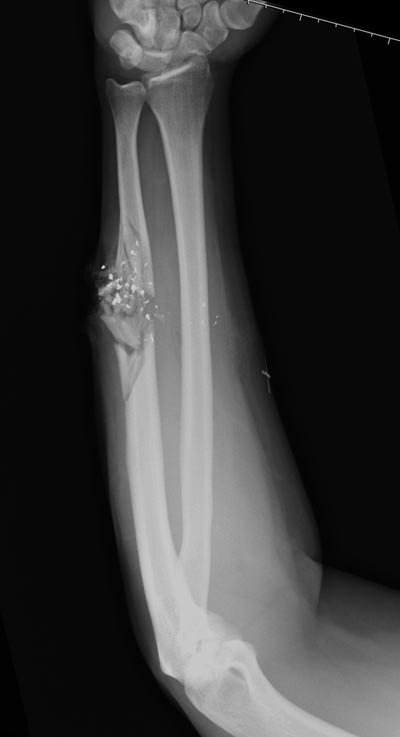

Здесь примеры: двоюродные братья с ранением предплечья, у одного

локтевая, а у второго лучевая. В следующее утро локтевая фиксирована без

обнажения фокуса травмы из небольших доступов, а второй из обычного

волярного доступа. А клинический снимок из прошлых операций...

Вложение не в текстовом формате было извлечено…

Имя     : GSW radius 3.jpg

Тип     : image/jpeg

Размер  : 38012 байтов

Url     : http://weborto.net:8080/pipermail/ortho/attachments/20140728/123f732a/attachment-0012.jpg